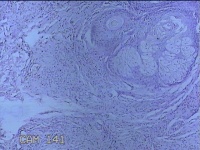

面部、下颌肿物

性别

女

年龄

36岁

临床诊断

皮脂腺囊肿

一般病史

无

标本名称

大体所见

灰白暗红色带皮肤样肿物1.3x0.8x0.3cm一个,表面光滑,起开肿物呈实性,切面灰白暗红色,质软。